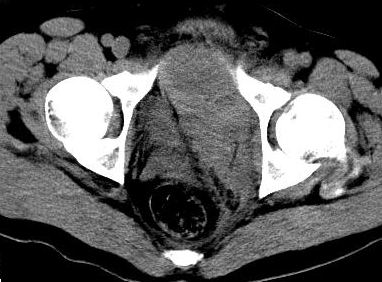

标题: CT8132:转贴:男,38岁,腹部压伤后腹痛、休克入院检查。 [打印本页]

标题: CT8132:转贴:男,38岁,腹部压伤后腹痛、休克入院检查。

本例支持盆腔左侧巨大血肿。

盆腔左侧不均匀高密度影,周围锐利,与膀胱分界清晰,考虑肠系膜损伤盆腔内血肿形成。期待结果。

盆腔内巨大血肿,患者是否有骨盆骨折?

结果公布:腹膜外血肿和腹腔内出血,虽然都是出血,但诊断和治疗却截然不同。如果腹腔内出血,那么在输血抗休克同时还要急诊手术止血。而腹膜外血肿不同,因为腹膜外出血往往都是小静脉丛破裂出血,手术往往找不到出血部位,找到了也很难缝合止血,造成难以控制的大出血,危机病人生命。还有腹膜对出血有个束缚作用,相当于压迫止血,利于出血自止。所以对腹膜外出血往往采取保守治疗。当然,如果腹膜外出血止不住破入腹腔,那么病人往往预后极差,恐怕连“九死一生”都谈不上。

ct上鉴别两者:腹腔内出血没有固定形态,分散在腹腔内,肠间隙等部位,破裂出血处会有较多血液聚集有血块;由于膀胱直肠陷凹是腹腔的最低处,出血和积液会积聚在此处,液体较多时膀胱会呈向前受压改变。该片血肿可见包膜(其实是腹膜)膀胱向右侧受压移位,而膀胱是腹膜间位器官。所以诊断是腹膜外血肿。